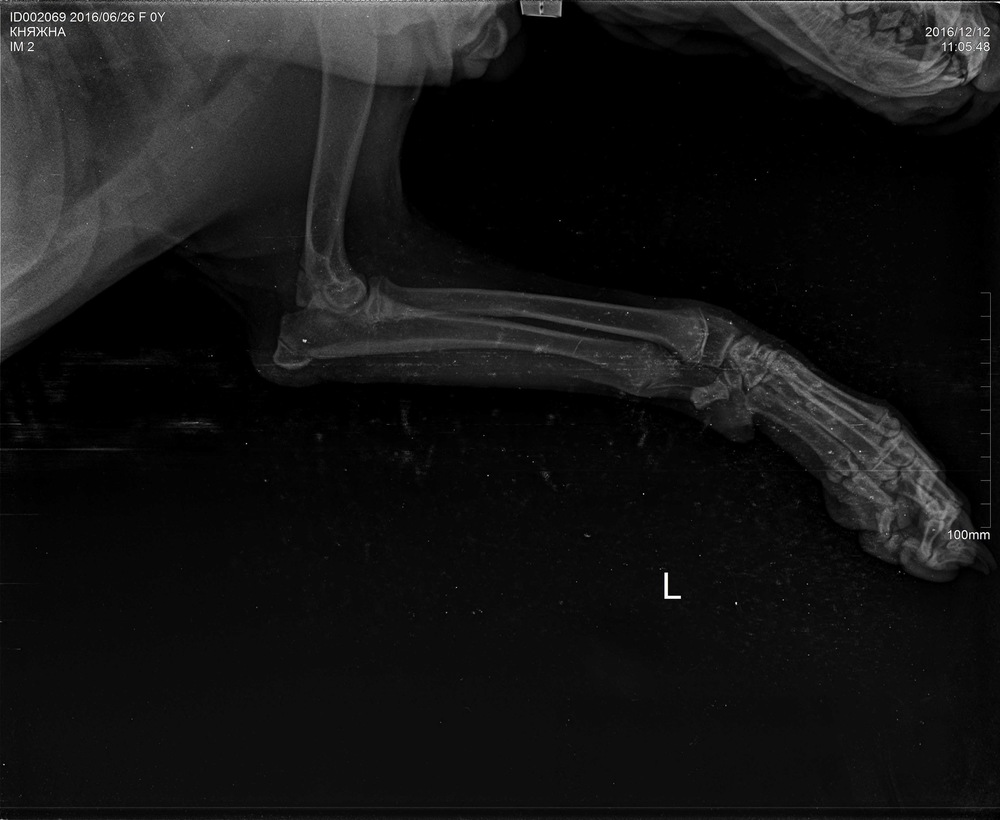

Рентген Задней Лапы Кошки: Нормы и Диагностика